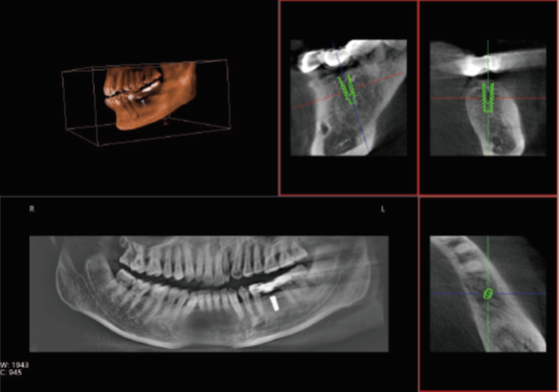

眾所周知,在口腔內種植牙齒是十分精細的手術,沒有先進的可視化影像設備支持的種植牙手術,就猶如盲人摸象,手術效果難以預知??谇籆T影像能測量牙槽骨的高度和寬度,估計種植部位,與下頜阻生磨牙相關的低位下牙槽神經管影響頜骨的疾病的病理學評估。

正常情況下,牙齒的排列不在一個平面上, 且具有一定的生理弧度,普通X線往往使圖像相互重疊,使圖片看不清楚。但是,口腔CT的三維成像對牙體、牙根、牙周膜等微細結構顯示更加清晰。可以幫助醫(yī)生了解斷根,牙根內吸收、根管鈣化、牙根結石、牙槽骨退縮等情況,能用于根管治療前尋找根管,術后評估根管充填情況,評估牙周炎程度及預期治療效果等。

正畸治療前的診斷分析是治療成功的重要步驟,口腔CT不僅能提供頭顱側位和曲斷片的信息,還可以評價每個牙齒的排列位置,牙根傾斜度,牙槽骨垂直向、頰舌向的骨量,骨密度等。用于牙列不齊矯正、牙頜面畸形矯正、牙周病輔助正畸。